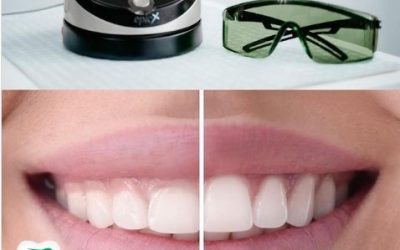

Zašto je važno da izbeljivanje zuba obavlja stomatolog?

Izbeljivanje zuba je jedan od najpopularnijih estetskih tretmana stomatologije danas. Ali zašto je važno da ovaj postupak obavlja stručnjak? Beljenje zuba ima za cilj da promeni boju prirodnih zuba i učini ih svetlijim. Faktori kao što su: duvan, konzumacija tamnih...